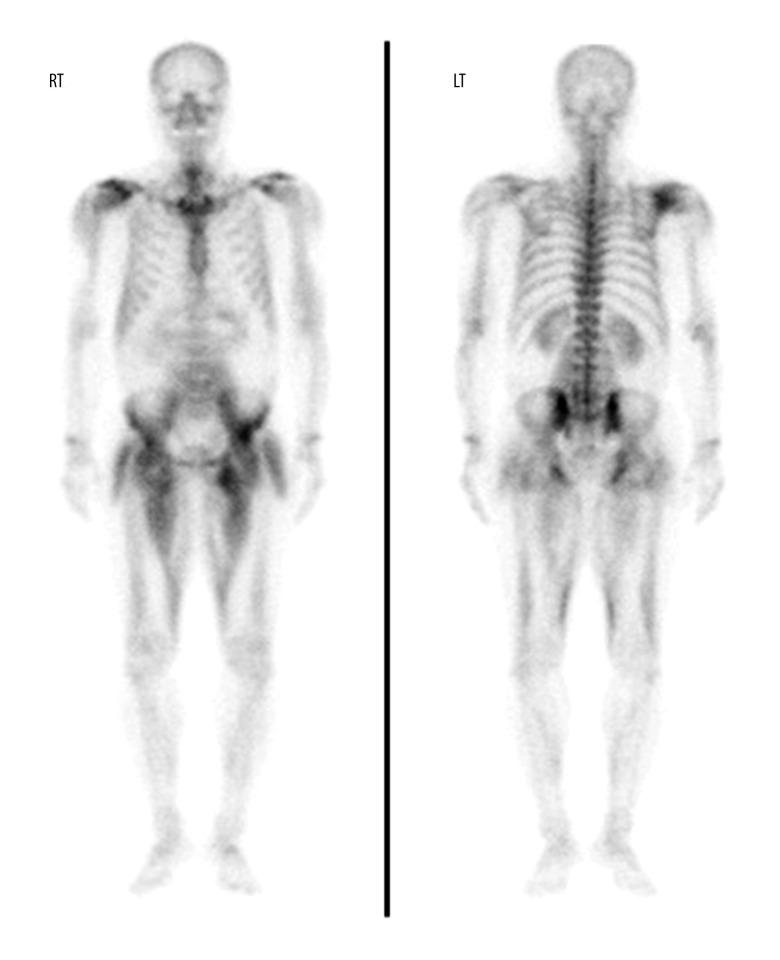

2

The clinical significance of technetium-99m methylene diphosphonate bone scintigraphy findings in patients with rhabdomyolysis.99m锝亚甲基二膦酸盐骨闪烁显像结果在横纹肌溶解症患者中的临床意义。

Nucl Med Commun. 2017 Oct;38(10):820-825. doi: 10.1097/MNM.0000000000000709.